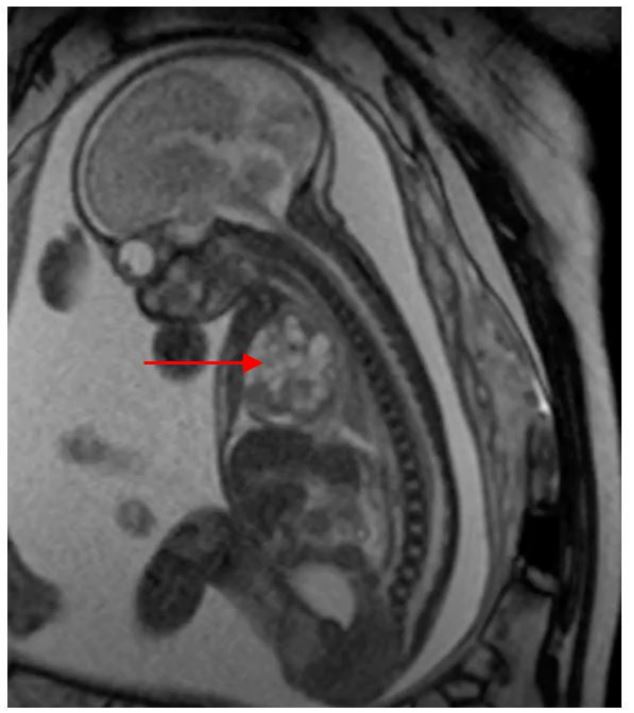

Fetal MRI at 29 weeks confirmed the suspected diagnosis of teratoma (Figure 2). Mild pleural effusion and ascites were noted, consistent with early signs of fetal hydrops.

Figure 2 MRI at 29 weeks showing a predominantly cystic mass in the right hemithorax. The red arrow indicates the mediastinal teratoma.